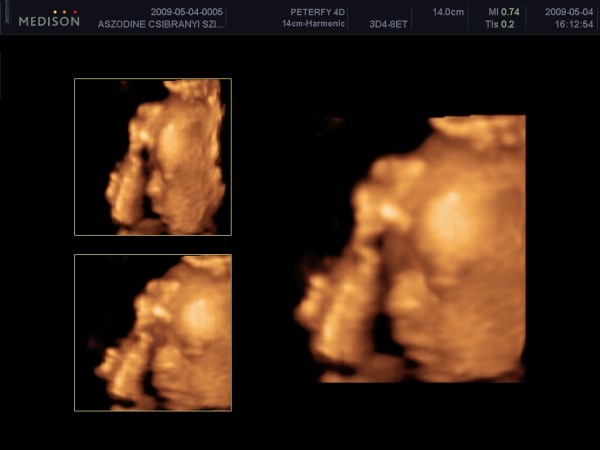

A pocakképek gyönöyrűek, mindenki szépen gömbölyödik, és mindenki gyönyörű kismama.